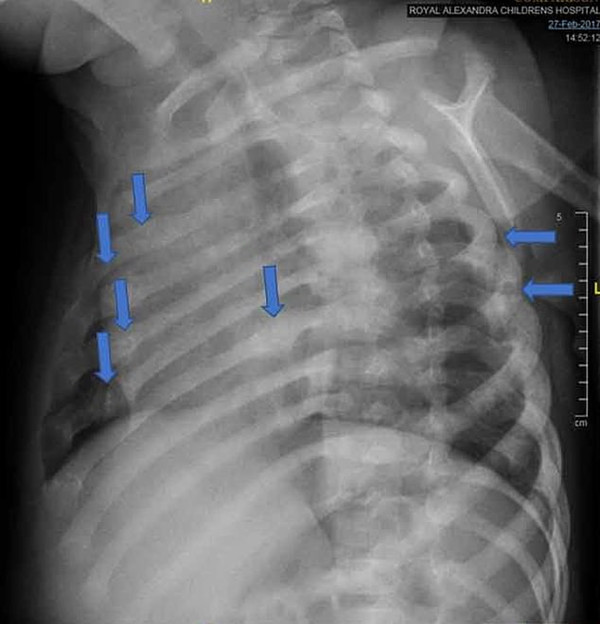

据报道,这起虐童事件于2017年2月曝光,当时这名男婴因手臂骨折被送往医院。这对夫妇向皇家萨塞克斯郡医院的医生谎报了男孩的痛苦以及他受重伤的原因,声称孩子被地毯凸起的一角绊倒了。后来医院发现男孩的伤势十分严重,肋骨骨折20处,膝盖、脚踝和都有骨折。儿科医学专家获取的证据显示,这些伤害是由强力所致,男孩骨折处是由于故意扭转、挤压造成的。医院确认骨折是在孩子被送到医院之前的四到六周之间造成的。